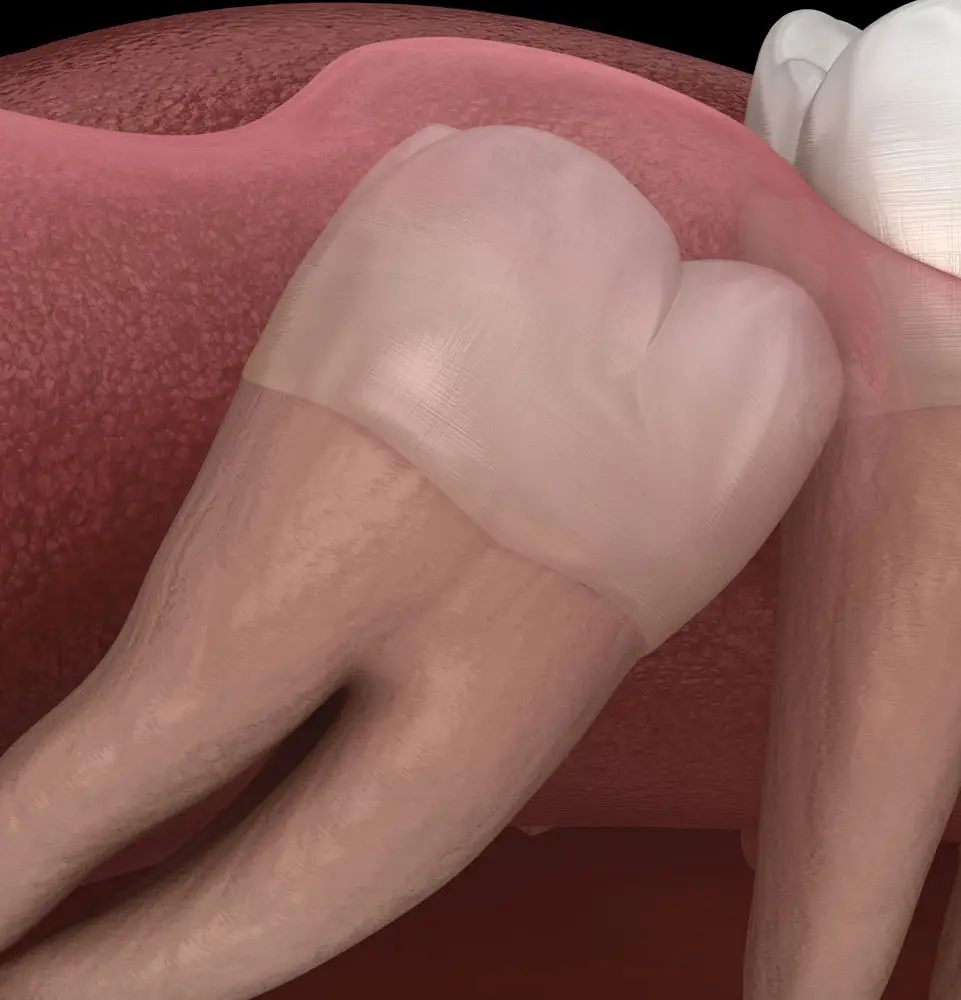

Wisdom teeth often spell trouble. Due to limited space, these teeth can pressure neighboring teeth, causing shifting and crowding issues. In more severe cases, they can become impacted within the jawbone, posing a risk to the health of adjacent teeth and bone structure and even leading to infections.

The typical age for a wisdom tooth extraction falls between 16 and the early 20s. For many, wisdom tooth extractions mark their first encounter with surgical procedures. We recognize the significance of ensuring a smooth and comfortable experience during this process.